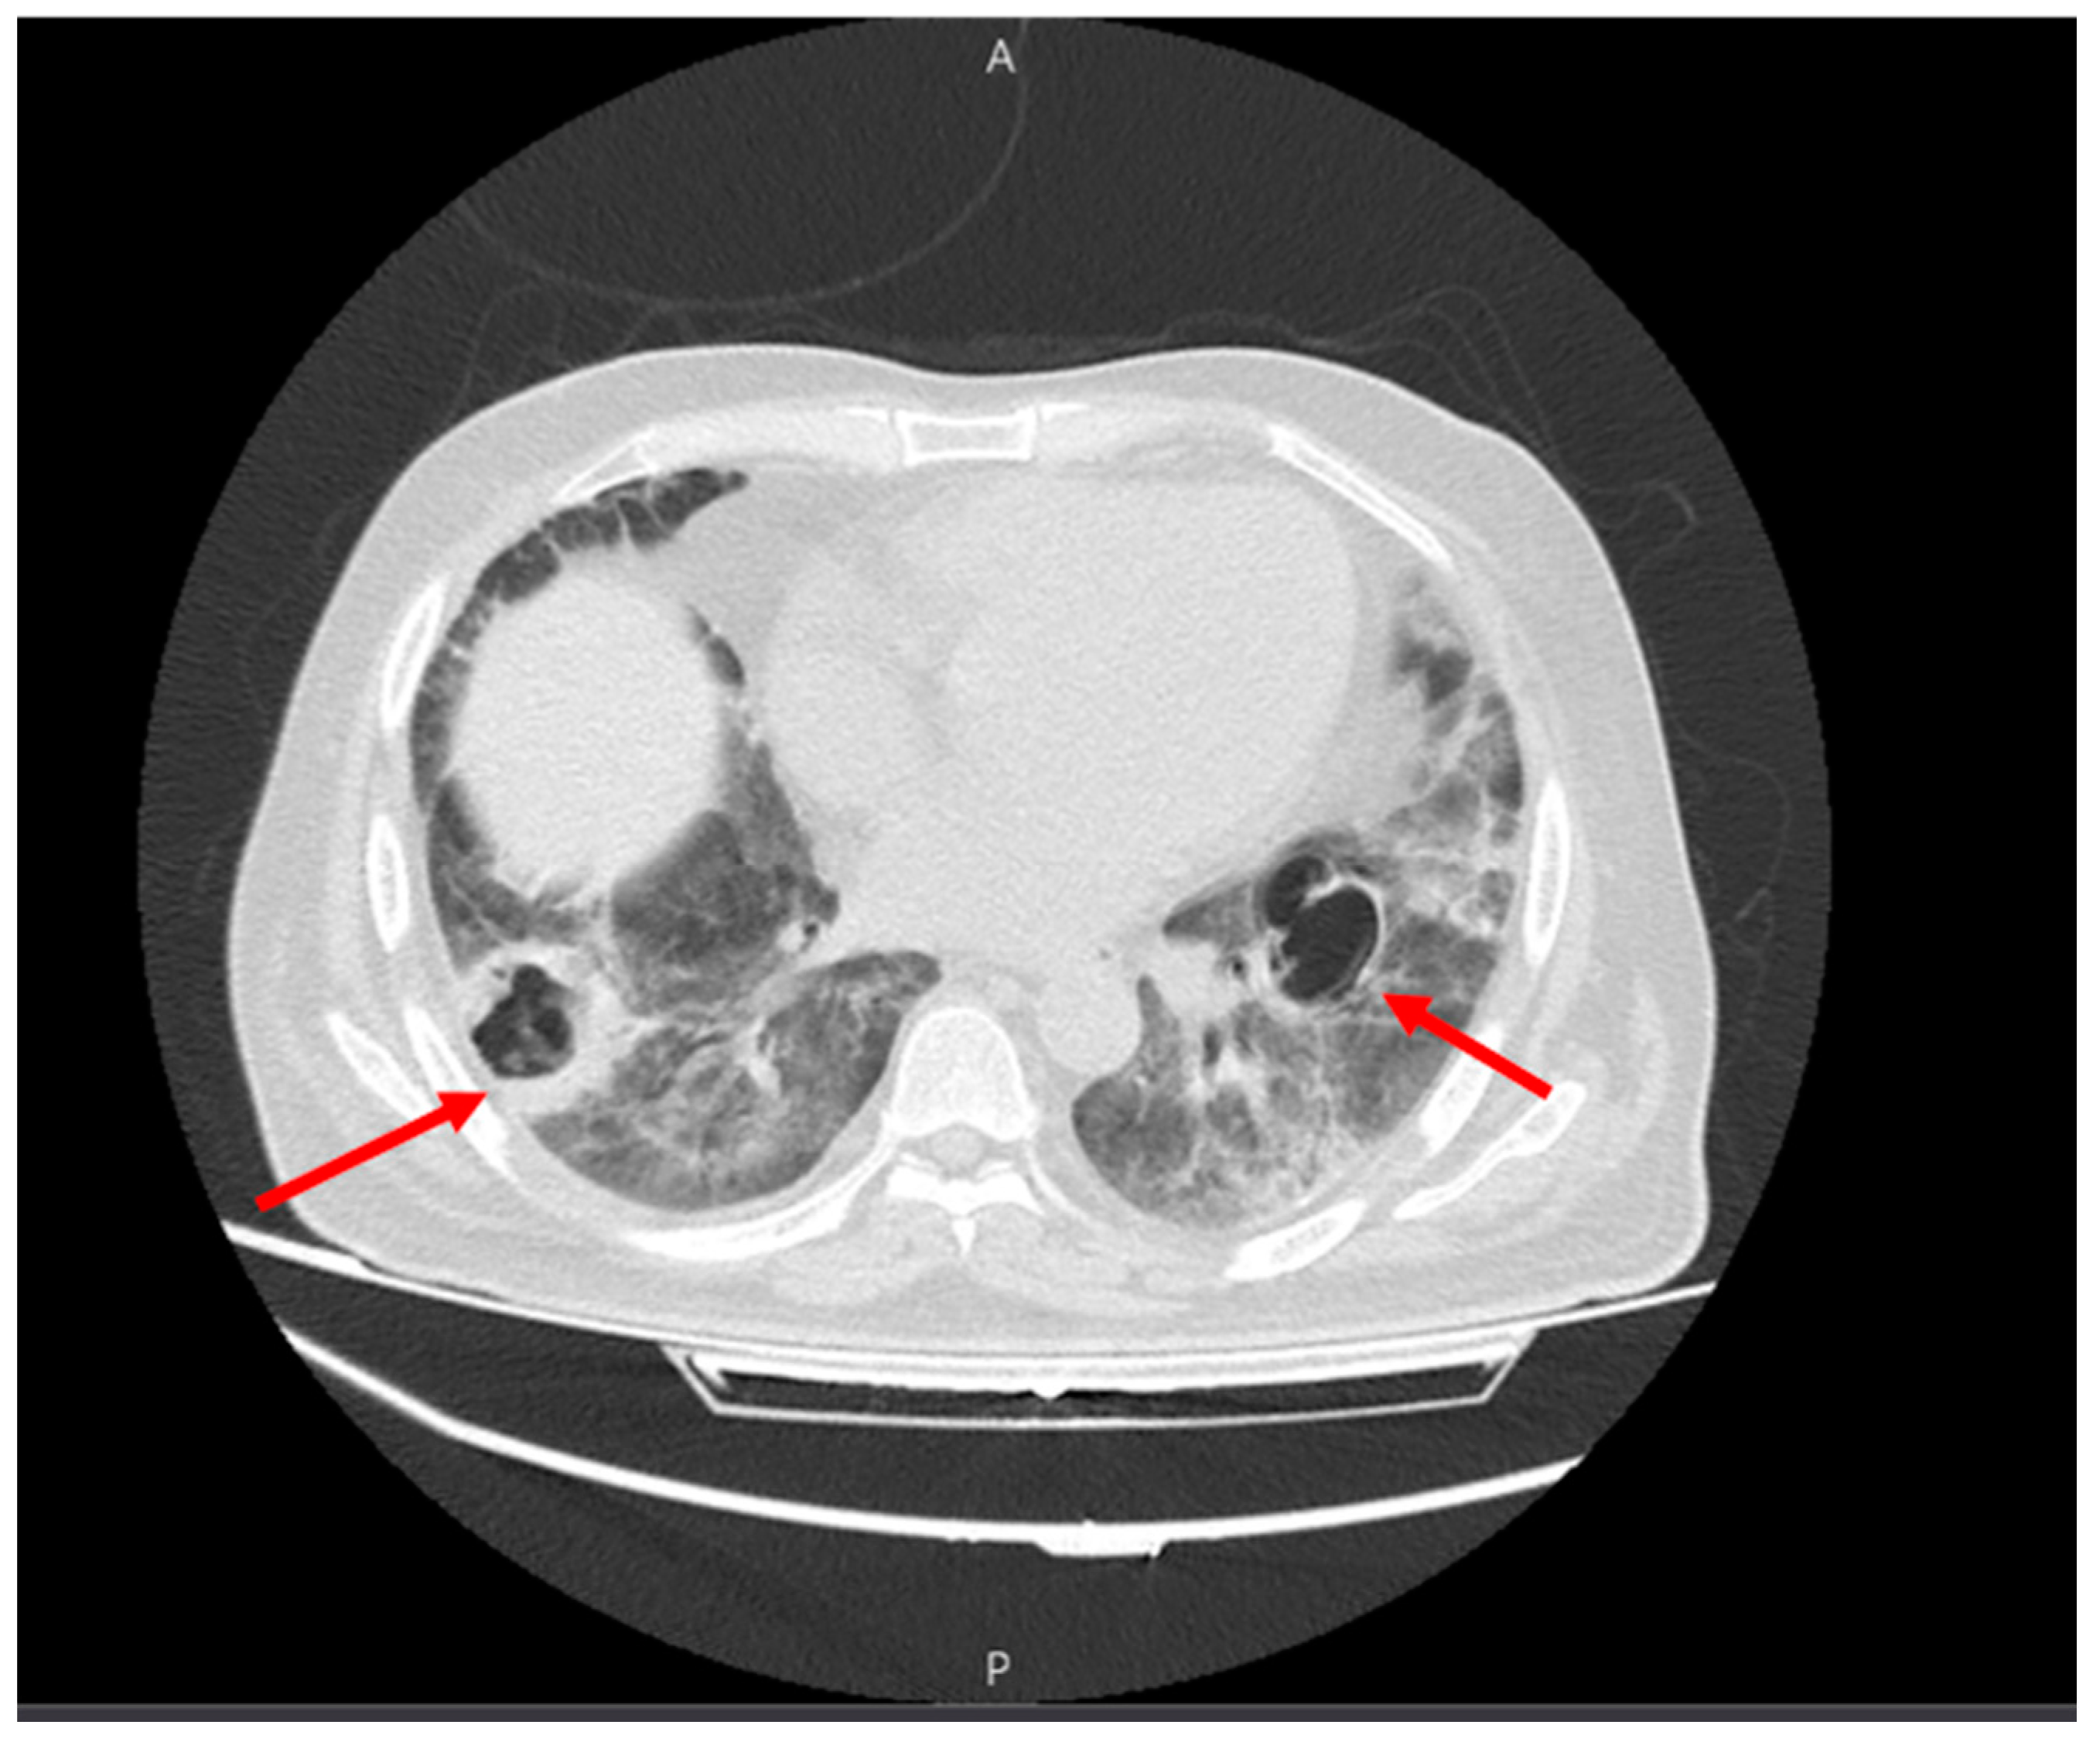

Figure 3.

Multiple cavities with thick, septoid walls in the lower lobes on both sides (red arrows).